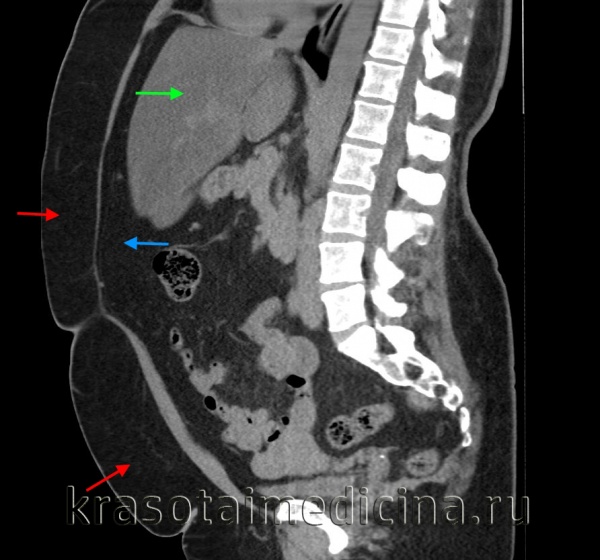

КТ ОБП. Избыточное количество висцеральной жировой клетчатки у пациента с повышенным индексом массы тела.